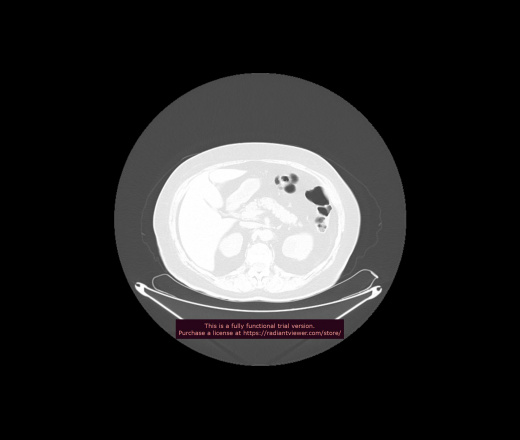

Уважаемые коллеги, если имеется интерес, сможете ли Вы спрогнозировать дальнейшее +-одинаковое течение процесса у 4 данных разных пациентов? Зацепиться где-то можно очень просто, где-то нельзя.